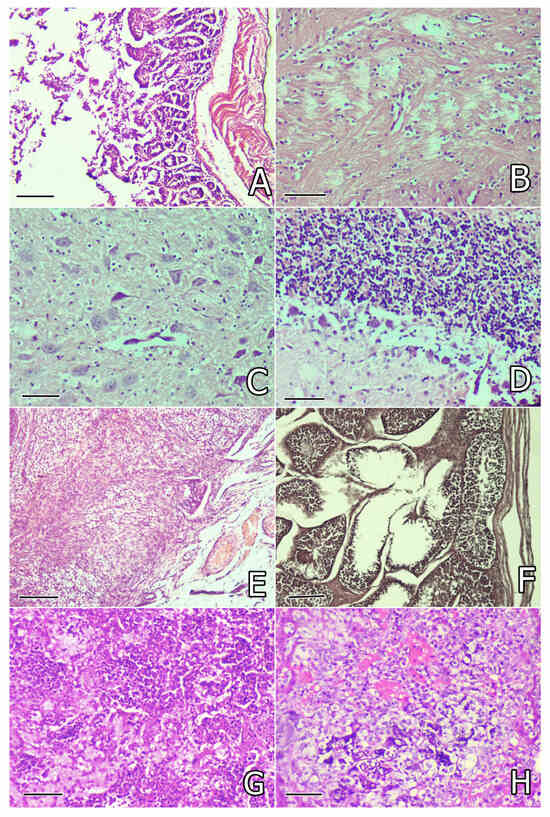

2.5. Pathomorphological Changes

2.5.1. Pathomorphological Changes on the 30th and 80th Day of the Study

2.5.2. Pathomorphological Changes in Rabbits That Died of Pasteurellosis

| Pathomorphological Changes | OTA + SIL | OTA + SM | OTA + WS | OTA + CA | OTA |

|---|---|---|---|---|---|

| Liver | |||||

| Degenerative lesions in hepatocytes | ++ | ++ | ++ | ++ | ++++ |

| Congestion or perivascular mononuclear infiltration | + | + | + | + | +++ |

| Activation of endothelial cells and Kupffer’s cells | + | + | + | + | ++ |

| Bile duct proliferation and fibrosis or edema around bile ducts | ++ | ++ | + | + | +++ |

| Focal necroses and/or fibrin accumulation in rabbits with pasteurellosis # | - | ++ | - | ++ | +++++ |

| Kidneys | |||||

| Granular degeneration in proximal tubules | ++ | ++ | ++ | ++ | ++++ |

| Congestion of peritubular capillaries | + | + | + | + | ++ |

| Inflammatory cells infiltration in interstitium | + | + | + | + | +++ |

| Endothelial proliferation in peritubular capillary | + | + | + | + | ++ |

| Proliferation of connective tissue on the 80th day * | + | - | + | - | +++ |

| Sclerosis of some glomerules on the 80th day * | - | + | + | + | +++ |

| Tubular atrophy and retention cysts on the 80th day * | - | - | + | - | +++ |

| Thrombosis of some vessels (fibrin clots) in rabbits with pasteurellosis # | - | + | - | + | ++ |

| Lung | |||||

| Congestion of vessels and presence of siderocytes | + | + | + | + | ++ |

| Peribronchial or perivascular mononuclear infiltration | + | + | + | + | ++ |

| Focal catarrhal pneumonia | + | + | + | + | ++ |

| Purulent or croupous pneumonia and/or abscesses in rabbits with pasteurellosis # | - | +++++ | - | +++++ | +++++ |

| Fibrinous pleurisy and pericarditis, incl. adhesions in rabbits with pasteurellosis # | - | +++ | - | +++ | +++++ |

| Thrombosis (fibrin clots) in vessels in rabbits with pasteurellosis # | - | +++ | - | +++ | +++++ |

| Myocardium | |||||

| Vascular congestion | + | + | + | + | ++ |

| Mononuclear cells infiltration | + | + | - | + | ++ |

| Slight granular degeneration and/or lytic changes | + | + | + | + | ++ |

| Strong granular degeneration and/or thrombosis (fibrin clots) in vessels in rabbits with pasteurellosis # | - | ++ | - | ++ | +++++ |

| Spleen | |||||

| Degenerative lesions in white pulp | - | + | - | + | ++ |

| Depletion of cells in white pulp | - | + | + | ++ | +++ |

| White pulp reduction and predomination of red pulp in rabbits with pasteurellosis # | - | ++ | - | ++ | +++ |

| Thymus | |||||

| Degenerative lesions or depletion of cells in cortex | + | + | + | ++ | +++ |

| Intestines | |||||

| Degenerative lesions of surface/glandular epithelium | + | + | + | + | ++ |

| Brain | |||||

| Lytic/pyknotic changes in tigroid substance of neurons | + | + | + | + | ++ |

| Lytic changes in brain substance | + | + | + | + | ++ |

| Pericapillary and pericellular edema | + | + | + | + | ++ |

| Pericapillary infiltration with lymphocytes | - | - | - | - | ++ |

| Focal proliferation of microglia | - | - | - | - | ++ |

| Cerebellum | |||||

| Lytic changes in lamina medullaris or Purkinje cells | + | + | + | + | ++ |

| Ovary | |||||

| Connective tissue proliferation and interstitial edema on the 80th day * | + | + | + | + | ++ |

| Vascular congestion | - | - | - | - | + |

| Testicles | |||||

| Degenerative lesions in seminiferous tubules on the 80th day * | + | + | + | + | ++ |

| Interstitial edema on the 80th day * | + | + | + | + | ++ |